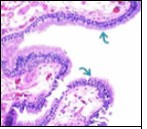

Cutaneous ciliated cyst is layered with a singular layer of ciliated epithelial cells which are chiefly constituted by cuboidal to columnar epithelium, traversed by partially configured fibrous tissue septa with an admixture of randomly dispersed, intraluminal papillary projections akin to those cogitated in the fallopian tube. Superimposed epithelium is inundated with well vascularized, parallel bundles of collagen although smooth muscle is absent 7, 8.

Cystic structures cogitated within deep dermal or subcutaneous tissue can be impacted with haemorrhagic fluid. Cyst lining is smooth, regular and is essentially composed of a singular layer of columnar epithelium with focally pseudostratified columnar epithelium, a circumscription of loosely configured, well vascularized, fibroconnective or fibrocollagenous tissue and an absence of inflammatory infiltrate.

Alternatively, cutaneous ciliated cyst can be lined by non ciliated cuboidal or columnar epithelium with intermingled intercalated, dark or round peg cells. Foci of squamous metaplasia can be occasionally exemplified in the adherent epithelium whereas mucinous cells or apocrine-like features are exceptional 6, 8. Figure 1, Figure 2, Figure 3, Figure 4, Figure 5, Figure 6, Figure 7, Figure 8, Figure 9, Figure 10, Figure 11, Figure 12. 11, 12, 13, 14, 15, 16, 17, 18, 19.

Figure 2.Ciliated cutaneous cyst with an undulating layer of ciliated cuboidal epithelium and supporting fibrous tissue framework (12).